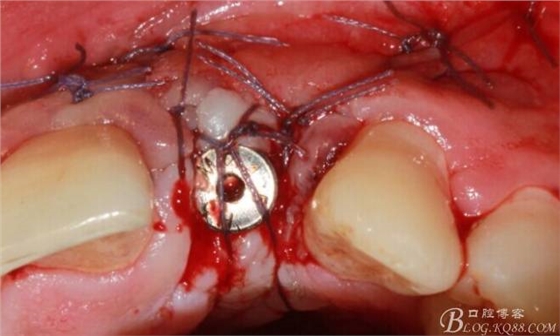

縫合。